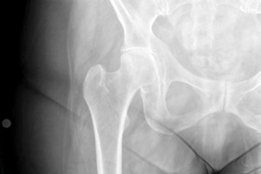

Can you describe the radiograph? This is an AP radiograph of the right hip. There is a pathological fracture …

Advanced osteoarthritis bilaterally. Osteonecrosis and complete obliteration of the joint space on both sides…